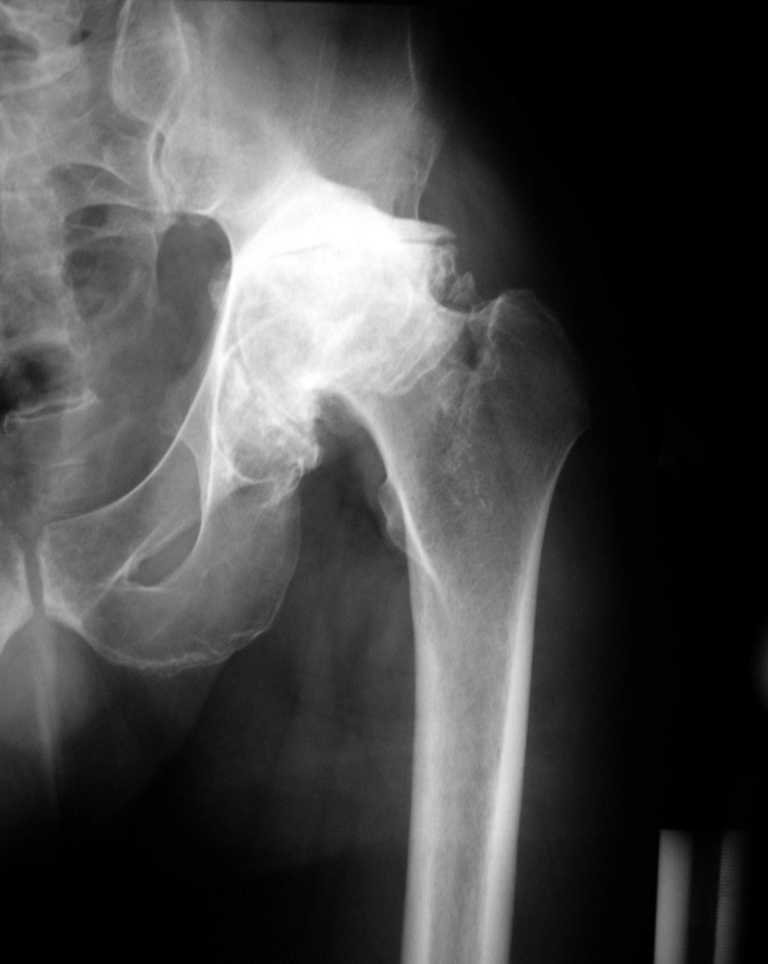

К нам обратился житель Казахстана с застарелым вывихом бедра. Травма год назад, вместо синтеза заднего края казахскими умельцами установлена клинковая пластина, через 6 мес удалена. Больной ходит с тростью,сгибание в т-б 90, разгибание 170, укорочение 5 см, боли не выражены, анальгетиками не пользуется. Настроен на эндопротезирование в клинике, где есть опыт подобных операций (возможно за рубежом).Наш план: аппарат таз-бедро, постепенное низведение бедра, "октопус" с пластикой. Но с такими большими дефектами мы не сталкивались.Есть вариант сначала аппарат, затем реконструкция впадины, протез обычный через 4-6 мес.Есть мнение не восстанавливать длину. Будем признательны за полезные советы. Было бы интересно посмотреть пример.

Кстати, судя по рентгенограммам и КТ истинная разница в длине ног не столь велика, укорочение, главным образом, за счет контрактур.